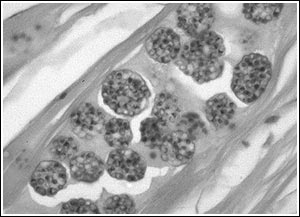

Microscopisch onderzoek:

Zoals al aangegeven, komen we Pleistophora tegen in de spieren van de vis. Dus moeten we ervoor zorgen dat we hier een prepraat van maken. Vervolgens gebruiken we een vergroting van 200x, waarna we vervolgens kunnen vergroten richting de 600 x voor verdere onderzoek om de sporen goed te onderzoeken.